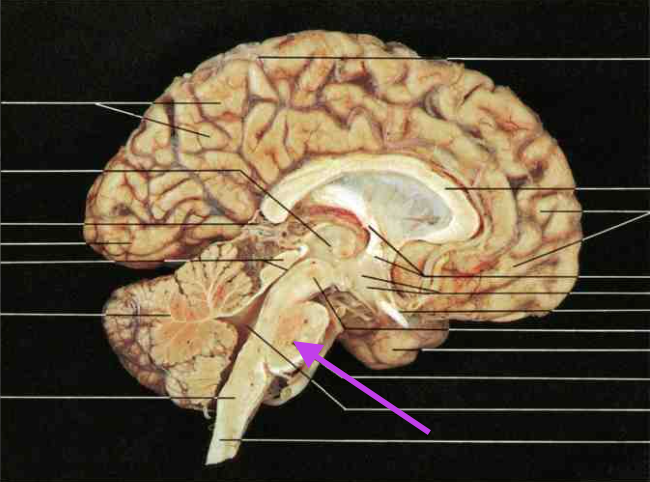

Midbrain. Section is Brain Stem.

Cerebral Aqueduct. Part of Midbrain. Section is brain stem.

Inferior Colliculus. Part of the midbrain. Section is brain stem.

Superior colliculus. Part of midbrain. section is brain stem.